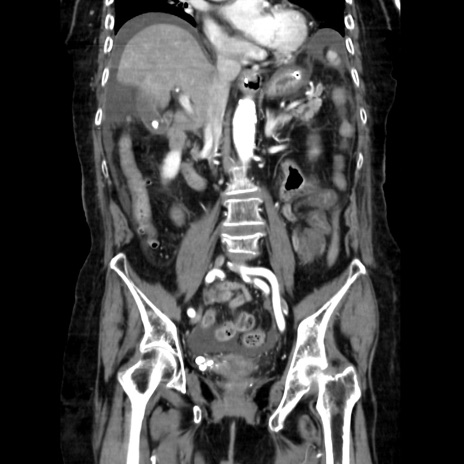

症例40(冠状断像)

【症例】90歳代女性

【主訴】腹痛・嘔吐

【現病歴】 食欲低下、嘔吐があり昨日他院受診。肺炎と診断され入院となる。入院後より腹部全体に圧痛あり。胃管留置され経過みていたが、症状持続するため、

当院転院となる。

【既往歴】胸椎圧迫骨折、胆石症

【身体所見】腹部:中央に激痛あり、圧痛あり、反跳痛不明

【データ】WBC 17100、CRP 18.82

冠状断像